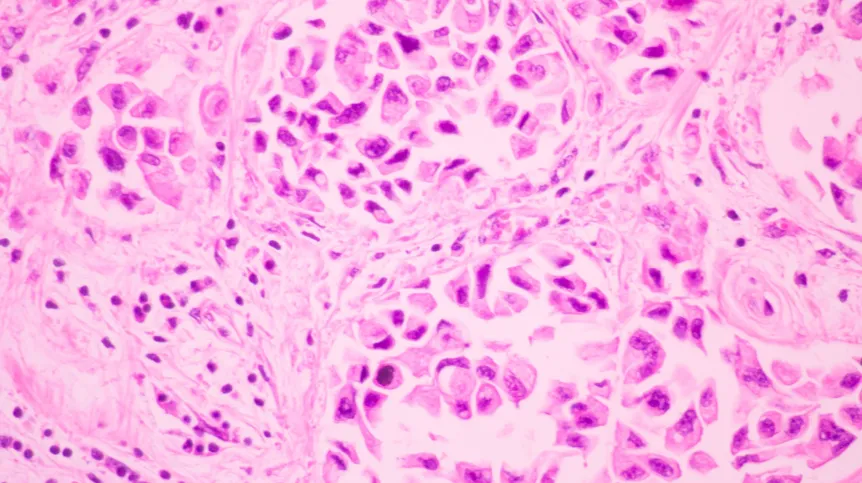

Proces akumulacji mutacji genetycznych prowadzących do rozwoju nowotworów piersi i jajnika można lepiej zrozumieć dzięki modelowi Avramiego-Dobrzyńskiego, opracowanemu przez polskich naukowców. Fizycy wykorzystali analogię do sposobu powstawania kryształów. Analiza ryzyka może znacznie przyspieszyć diagnozę.

"Wielopunktowy model kancerogenezy zakłada, że nowotwór powstaje w wyniku sekwencyjnej akumulacji wielu mutacji genetycznych w komórkach, co prowadzi do zakłócenia prawidłowych funkcji komórkowych i rozwoju nowotworów złośliwych. Kiedy liczba mutacji onkogennych przekracza pewną wartość krytyczną, transformacja nowotworowa komórki przebiega jako szybki proces nieliniowy, analogicznie do zjawiska fizycznego przejścia fazowego" - wyjaśniono na stronie Politechniki Warszawskiej.

Badacze przeanalizowali dane dotyczące raka piersi i jajnika u podopiecznych Narodowego Instytutu Onkologii im. Marii Skłodowskiej-Curie w Warszawie. Okazało się, że u pacjentek z dziedzicznymi mutacjami genu BRCA1/BRCA2 nowotwór można zdiagnozować około dwóch lat wcześniej niż u pozostałych osób.